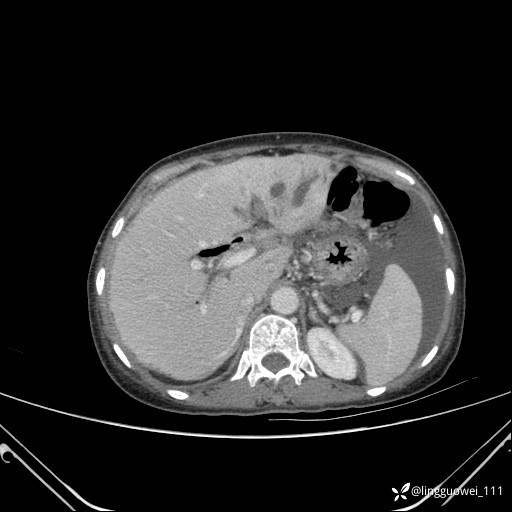

病例女,65岁,门诊行胃肠镜检查后,说腹胀入院检查,CT能发现病因吗?已公布结果

主诉:门诊行胃肠镜检查后,诉腹胀,入院检查,肝有病变吗?腹膜及腹腔的表现有特征性吗?

门脉期:

img